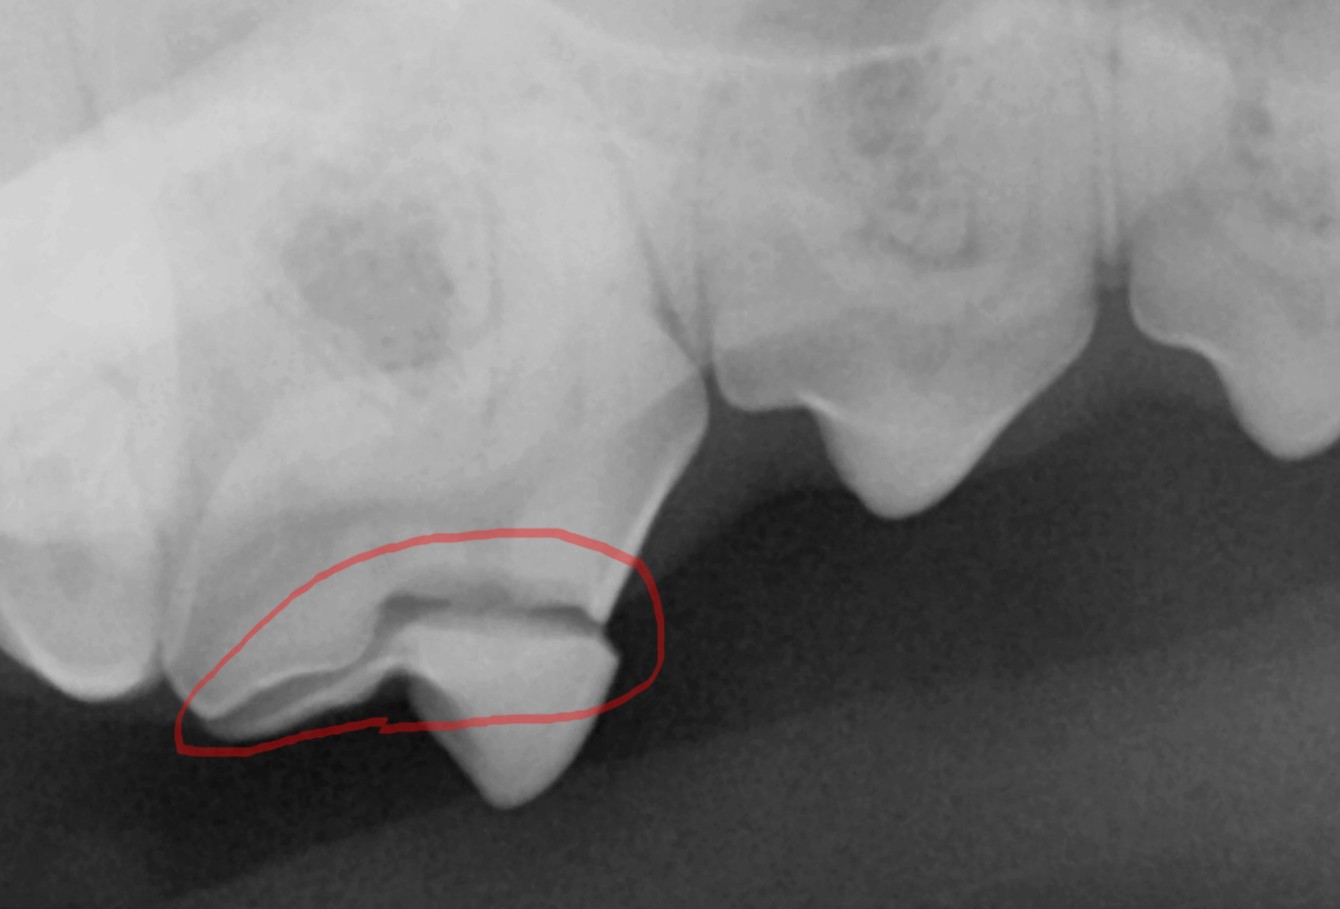

엑스레이 촬영을 통해 확인해 보니 그 부분은 단순한 착색이 아니라 법랑질과 상아질이 함께 손상된 복합 파절이었습니다.

외형상 단순하게 치석이 긴 치아처럼 보였지만, 확대 관찰을 해보니 표면이 매끄럽지 않고 치아 표면에 미세한 금이 간 것이 확인되었습니다. 이 부위는 단순한 착색이 아니라 법랑질과 상아질이 분리된 균열선, 즉 치아가 실제로 끊긴 치관 파절이었습니다.

엑스레이 촬영 결과도 같은 부위에서 방사선 투과선이 명확히 관찰되었습니다.

치관의 법랑질과 상아질 경계를 따라 이어지는 이 선은 단순 표면 손상이 아니라 치수강 바로 인접한 손상으로 확인되었습니다.

엑스레이 결과, 우측 상악 제4전구치(p4)는 법랑질과 상아질이 함께 손상된 복합 치관 파절로 확인되었습니다. 치수강 근처까지 금이 이어져 있어 보존 치료는 불가능했기 때문에, 결국 수술적 발치를 진행하기로 결정했습니다.